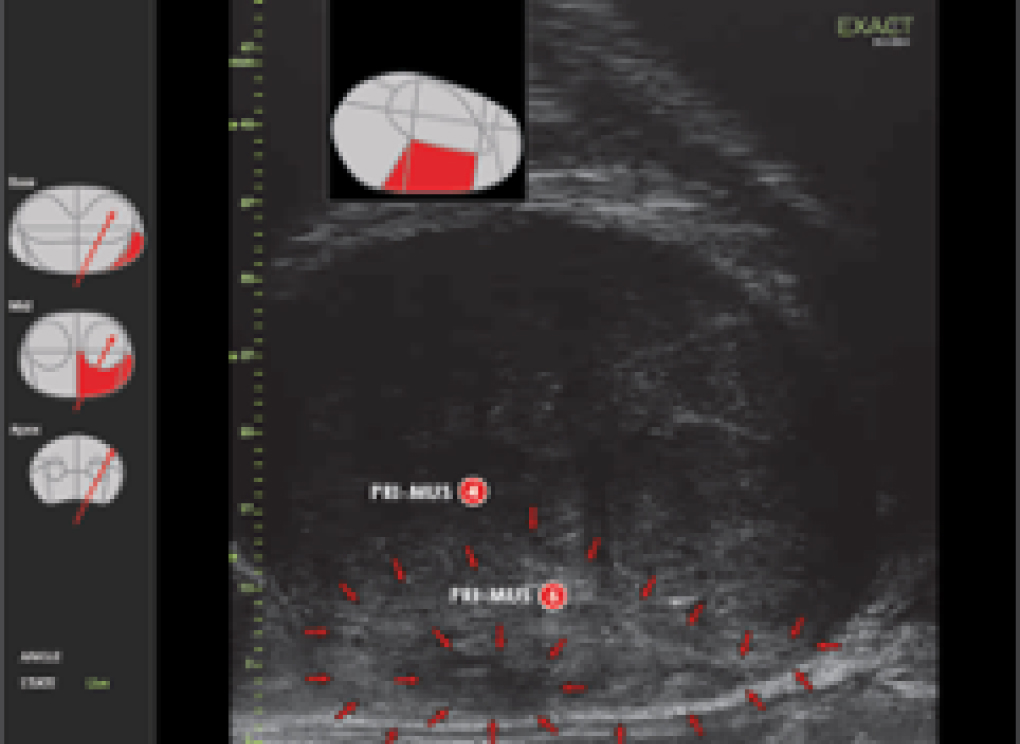

Exact Imaging's advanced systems provide high-resolution visualization and precise targeting of suspicious areas while also facilitating systematic biopsies for prostate cancer diagnosis.

Trusted by urologists worldwide, the ExactVu micro-ultrasound platform provides the most practical solution as a new tool for urologists to perform targeted biopsies within a standard urological workflow — fast, urologist-controlled, and completed in a single patient visit.